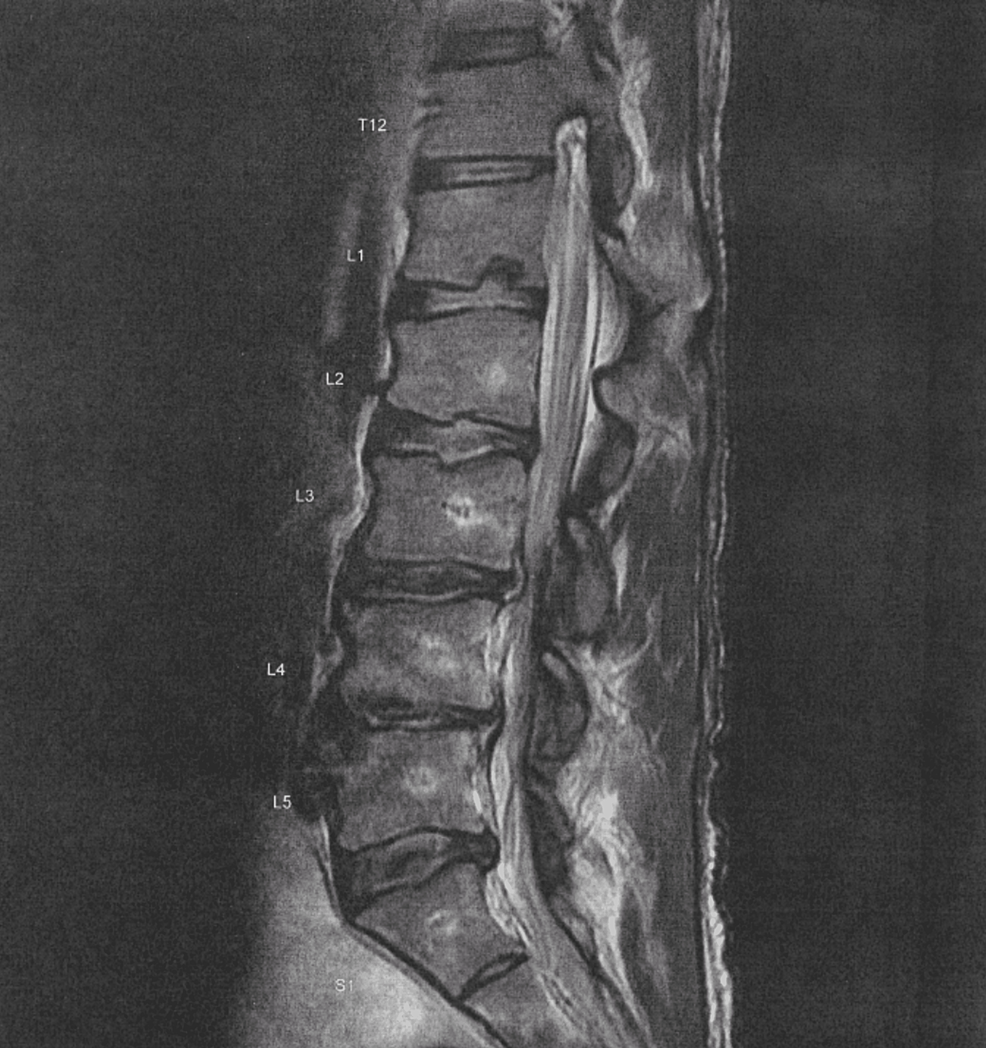

A 75yearold man with L3L4 and L4L5 spinal stenosis. A T2weighted What Is Narrowing Of L4 And L5 Sometimes, the ligament at the back of the lower spine, also called the lumbar spine,. Narrowing (stenosis) of bony openings for nerves due to the presence of bone spurs (abnormal bone growth) or other degenerative changes may cause compression of the nerve roots. Foraminal stenosis is a narrowing that affects spinal nerves in your back. Most people with it don’t. What Is Narrowing Of L4 And L5.

Preoperative MRI showing lumbar canal stenosis at L45 with anterior What Is Narrowing Of L4 And L5 Lumbar spinal stenosis is a narrowing of the spinal canal in the lower part of your back. Lumbar refers to segment of your spine that. Stenosis can cause pressure on your spinal cord or the nerves that go from your spinal cord to. Foraminal stenosis is a narrowing that affects spinal nerves in your back. Sometimes, the ligament at the. What Is Narrowing Of L4 And L5.